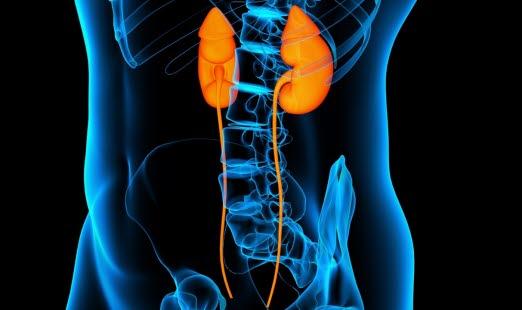

Nyrene

Nyrene er to knyttnevestore organer som ligger på hver sin side av ryggsøylen høyt oppe i bukhulen. Nyrene får blod fra hver sin nyrearterie, som er sidegrener til hovedpulsåren.

I nyrene skilles avfallstoffer og små mengder væske ut fra blodet slik at det dannes urin. På denne måten kvitter kroppen seg med skadelige stoffer. Nyrene har også en viktig funksjon ved å regulere mengden med salt og væske i kroppen. Når vi drikker mye, lager nyrene mer urin enn når vi drikker lite. Dermed beholder kroppen omtrent samme mengde væske uansett hvor stort inntaket er. For at avfallsstoffene skal kunne skilles ut, bør vi imidlertid drikke minst 1-2 liter vann hver dag.

I tillegg til dette bidrar nyrene til produksjon av noen hormoner som er med på å regulere blodtrykket. Disse hormonene kalles renin, angiotensin og aldosteron. Økt utskillelse av disse hormonene gir redusert urinproduksjon og sammentrekning av en rekke blodårer i kroppen. Dette fører til økt blodtrykk, hypertensjon. I noen situasjoner, for eksempel ved alvorlig væskemangel, er dette gunstig. Men i andre situasjoner kan det føre til skadelig høyt blodtrykk som noen ganger behøver behandling.